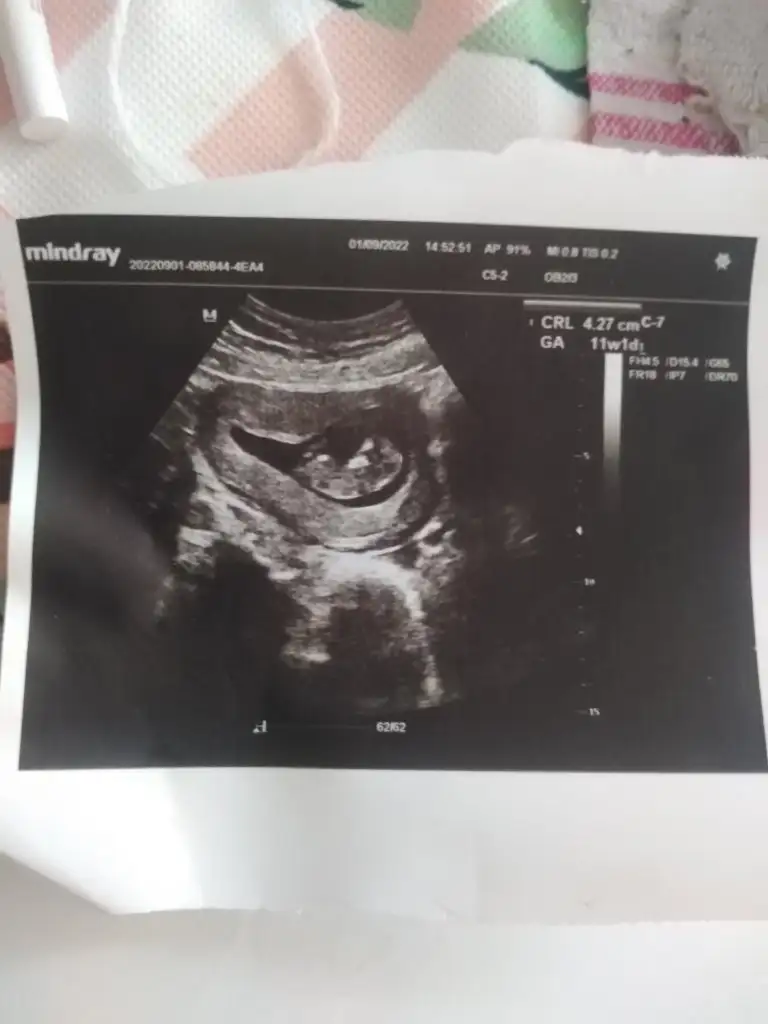

Kız gibiKızlar 16+3 haftalık hamileyim belli etmiyor kendini tahmin edermisiniz sizden ricam lütfen

Bir. Cok topige yazdim 4 kisi erkek dedi bir tek siz kız dediniz daha cok merak ettim tabiki yazarimHaber verin kesin olur mu

Bana da tahmin yapabilir misiniz :)Ultrasonu bu şekilde olup erkek olan çocuk görmedim . Bu zamana kadar hiç yanilmadim tahminlerimde.

%100 kiz demistiniz ama erkekmişBakalim carsamba gunu kontrolum var doktorum ne diycek